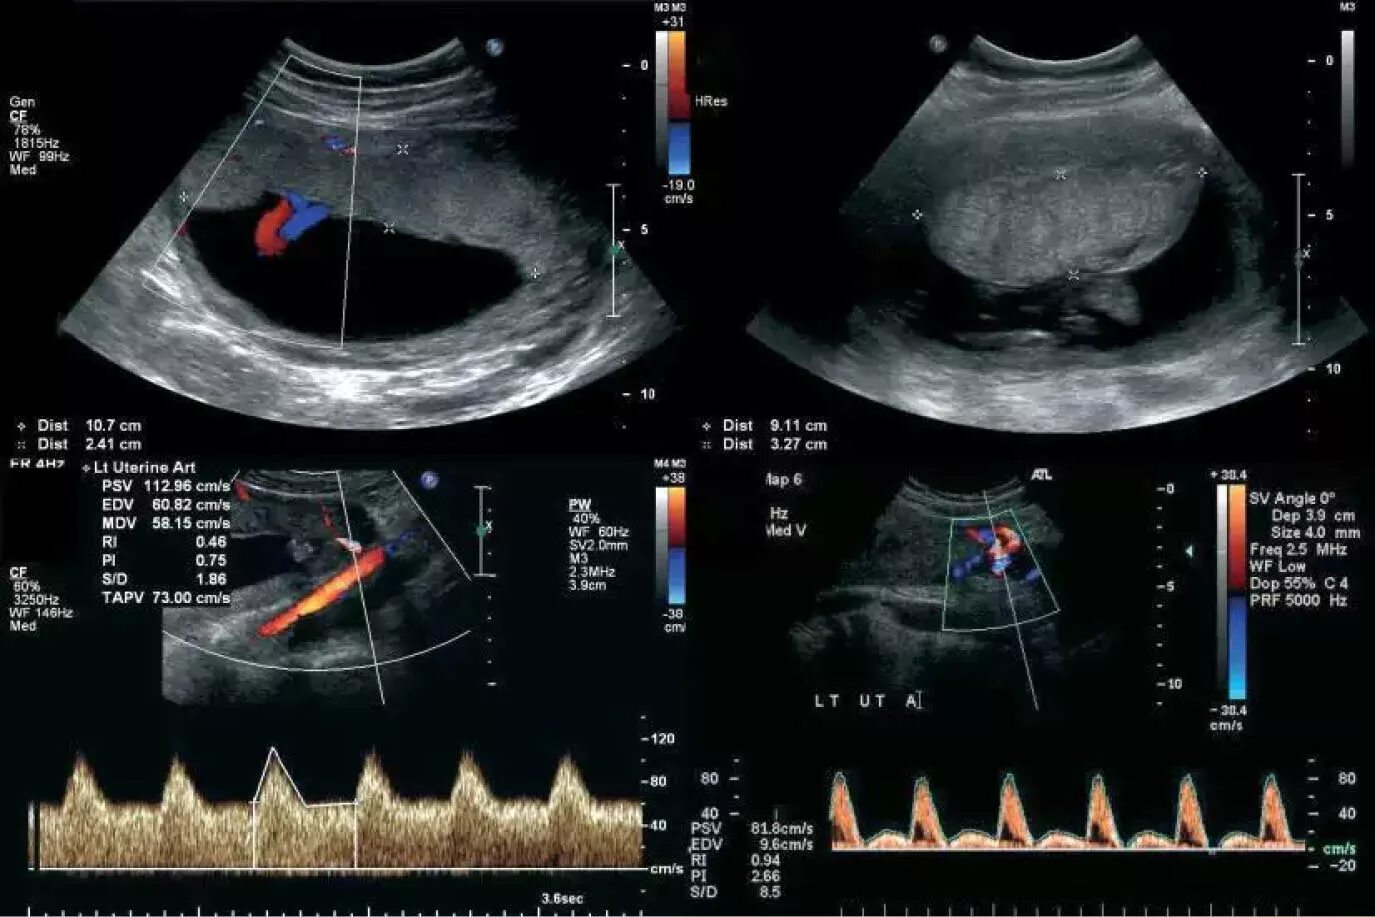

Допплерометрия маточных